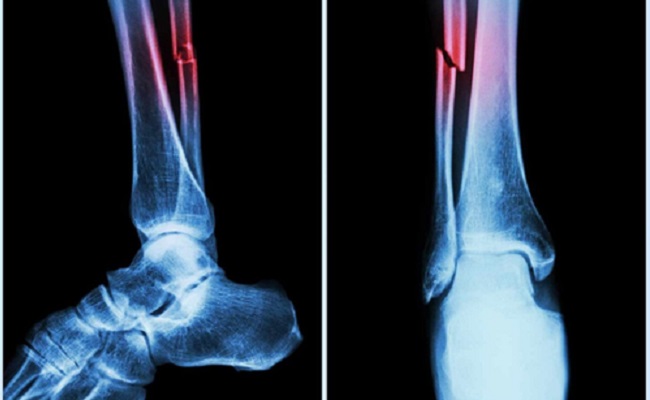

In the study, mice who had Covid-19 showed significant bone loss. This loss decreased the bone mechanical strength and increased the risk of fractures.

If similar bone loss occurs in human patients following their Covid‐19 recovery, it could leave them with a long‐term -- even permanent -- increased risk of fractures due to fragile bones. This is especially true in elderly patients.

The study suggested that the higher risk of fragility fractures, when a person falls from standing height or less, may be one of the underreported long-haul symptoms of Covid.